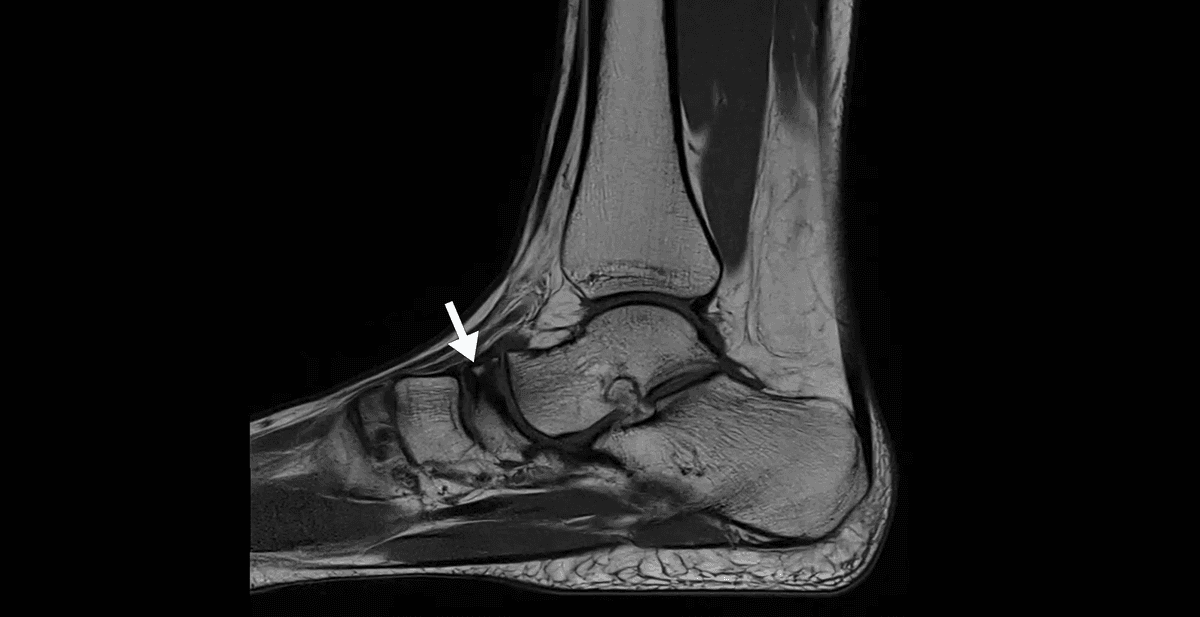

Cas d'une maladie de Köhler, ostéochondrose rare de l'os naviculaire du pied.

MRI